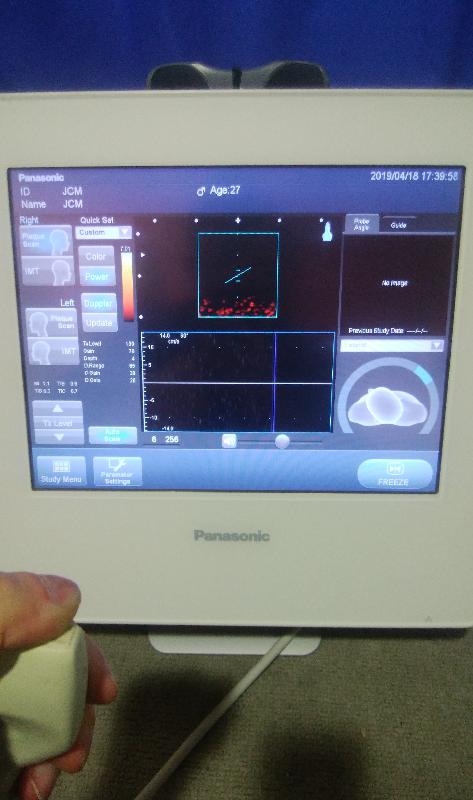

超音波診断装置|GEヘルスケア|PRODUCT_CODE]|中古医療機器の, 在庫情報|中古医療機器のジャパンセントラルメディカル,

在庫情報|中古医療機器のジャパンセントラルメディカル, 旭川医科大学 臨床シミュレーションセンター,